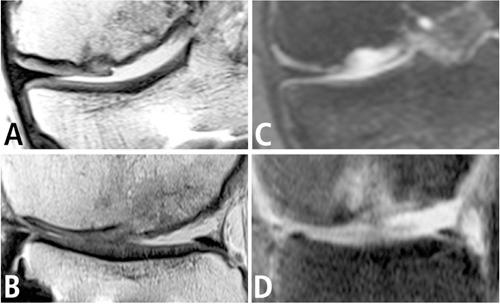

Treatment of osteochondral lesions of the knee remains a major challenge in orthopedic surgery. Recently established procedures like autologous chondrocyte implantation or matrix-associated chondrocyte implantation yield good results, but include the disadvantage of two-step procedures. The purpose of this study was to evaluate the clinical and magnetic resonance imaging outcome of repairs of osteochondral defects of the knee by a combined procedure of bone grafting and covering with a bilayer collagen membrane in a sandwich technique. Seven male patients with a mean age of 42 (range 30-55) years and symptomatic focal osteochondral lesions of the knee grade IV according to the International Cartilage Repair Society classification were included. The mean diameter of defects was 28.6 (range 15-40) mm. Results were evaluated at a minimum of 24 months after surgery by International Knee Documentation Committee score, Lysholm-score, visual analogue scale, and magnetic resonance imaging with specific cartilage sequences, evaluating the ICRS score and the Magnetic Observation of Cartilage Repair Tissue (MOCART) score. All patients judged the operation as successful. Among the patients available for the long-term follow-up, mean visual analogue scale value was 1.3 (range 0-3) out of 10 points. Mean International Knee Documentation Committee score was 80.8 (range 63.2-88.5) out of 100 points. Mean Lysholm score was 85 (range 55-95) out of 100 points. None of the patients had to be reoperated until today. Evaluation of magnetic resonance imaging using the MOCART score revealed a good correlation to the clinical outcome. This is the first study reporting results after reconstruction of osteochondral defects of the knee joint by bone grafting and a bilayer collagen membrane. This new method offers the advantage of a one-step-procedure and yields both good clinical and magnetic resonance findings. We conclude that this procedure can be a valuable tool to improve joint function after osteochondral defects, trauma, and in joints with local arthritic lesions.

膝关节骨软骨损伤的治疗仍是骨科手术中的一项重大挑战。近期开展的一些手术,如自体软骨细胞植入或基质相关软骨细胞植入,虽取得了良好效果,但存在需分两步进行的缺点。本研究的目的是评估采用三明治技术,通过骨移植并用双层胶原膜覆盖的联合手术修复膝关节骨软骨缺损的临床及磁共振成像结果。纳入了7名男性患者,平均年龄42岁(范围30 - 55岁),根据国际软骨修复协会分类,患有膝关节IV级有症状的局灶性骨软骨损伤。缺损的平均直径为28.6毫米(范围15 - 40毫米)。术后至少24个月,采用国际膝关节文献委员会评分、Lysholm评分、视觉模拟量表,以及使用特定软骨序列的磁共振成像进行结果评估,评估国际软骨修复协会评分和软骨修复组织磁共振观察(MOCART)评分。所有患者均认为手术成功。在可进行长期随访的患者中,视觉模拟量表平均评分为1.3分(范围0 - 3分,满分10分)。国际膝关节文献委员会平均评分为80.8分(范围63.2 - 88.5分,满分100分)。Lysholm平均评分为85分(范围55 - 95分,满分100分)。截至目前,无一例患者需要再次手术。使用MOCART评分对磁共振成像进行评估,结果显示与临床结果具有良好相关性。这是第一项报告通过骨移植和双层胶原膜重建膝关节骨软骨缺损后结果的研究。这种新方法具有一步法的优势,临床和磁共振成像结果均良好。我们得出结论,该手术可成为改善骨软骨缺损、创伤后及局部关节炎性病变关节功能的一种有价值的手段。